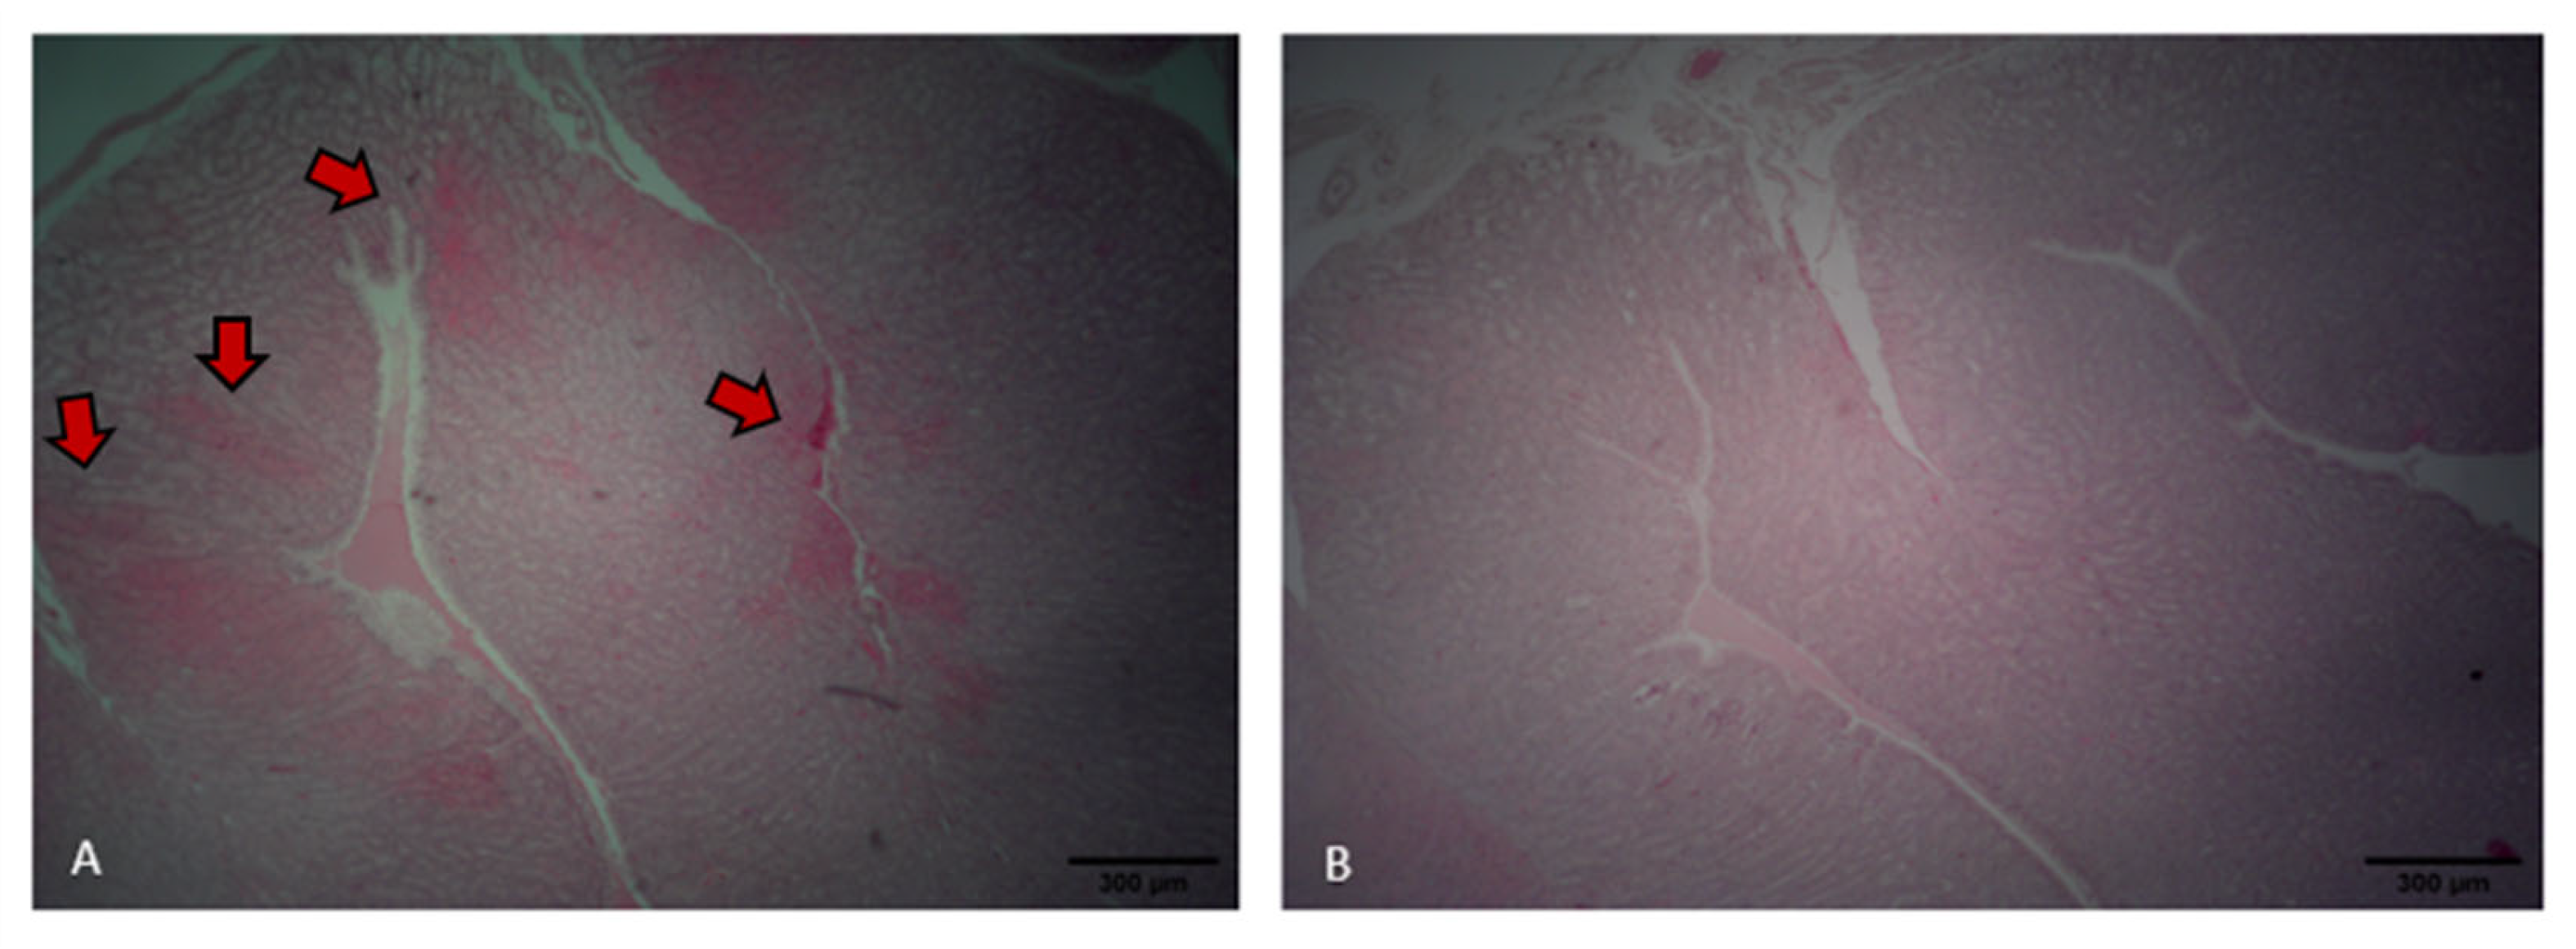

2.3.2. Oviduct Morphology